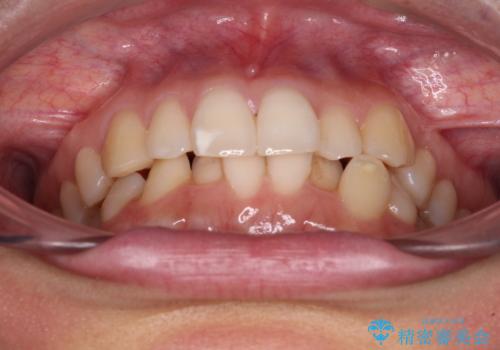

- 上下のクロスバイトと前歯のデコボコを気にして来院された患者様です。

インビザラインを用い、IPR(歯と歯の間を削る)と歯列全体を拡大させることで、歯並びを整えていくこととしました。

下の歯が隠れてしまうほどでしたが、深い咬み合わせも改善され、顎への負担も軽減されました。